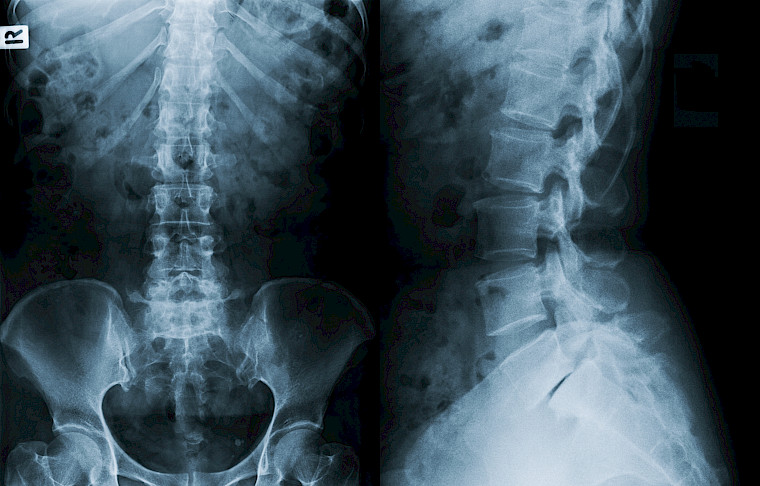

Unsere klinisch orientierte Radiologie präsentiert eine vielfältige Palette an bildgebenden Untersuchungen.

Hierzu gehören Röntgenaufnahmen, Computertomographie (CT), Magnetresonanztomographie (MRT), Ultraschall und mehr. Mit modernsten Geräten ermöglichen wir präzise Diagnosen. Unser erfahrenes Radiologenteam setzt sich für eine schnelle und optimale Bildqualität ein, stets unter Berücksichtigung minimaler Strahlenbelastung. Die enge Kooperation mit Zuweisenden und internen Fachabteilungen gewährleistet eine nahtlose Versorgung. Unser Ziel ist es, rasche Ergebnisse für eine effektive Behandlungsplanung bereitzustellen. Individuelle Betreuung steht bei uns im Fokus, um den Bedürfnissen jedes Patienten gerecht zu werden. Vertrauen Sie auf modernste Technologie und Expertise für erstklassige Radiologie.

Digitales Röntgen

Sämtliche konventionelle Röntgenaufnahmen führen wir in digitaler Technik durch, inklusive Thorax-, Abdomen und Skelettaufnahmen. Die Röntgendokumentation erfolgt ebenfalls digital.

Das Angebot umfasst sämtliche konventionellen digitalen Röntgenaufnahmen für Thorax-, Abdomen- und Skelettaufnahmen, Ultraschalluntersuchungen für Weichteile, Ganzkörper-Computertomographie und MRI-Untersuchungen.